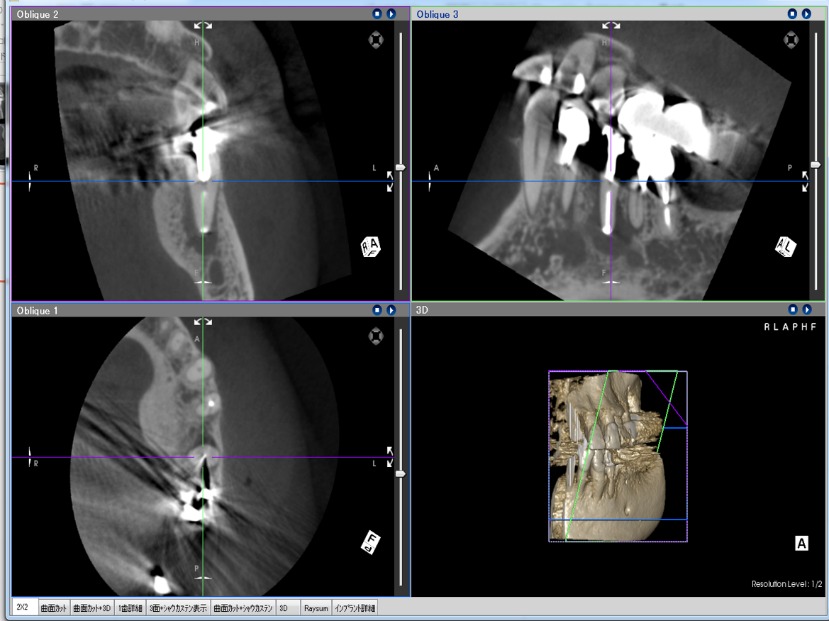

X線検査